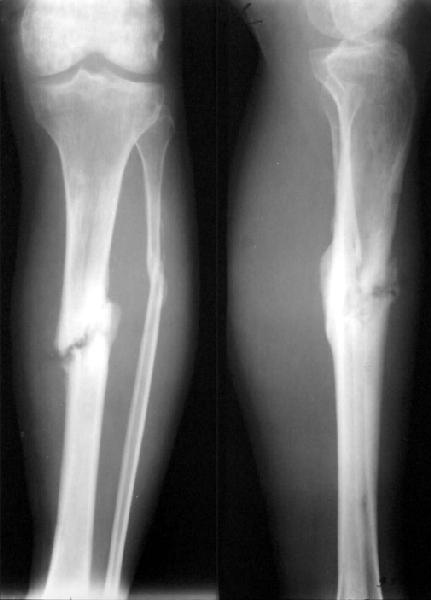

A male 26 y.o. sustained closed tibial shaft fracture after a car accident (pedestrian injury) Feb 7, 2002. In a small local hospital the Ilizarov fixator was applied, reduction was poor. 3 months later it was removed and replaced by plaster cast. The patient reported after ex-fix removal mobility at the site, no wire tract infection. A month later he himself decided to take off the cast. Now walks with cane and limp, marks pain over the site. No obvious mobility found at examination. Recent films (AP and 3/4) attached.

What diagnosis is correct to date? Pseudarthrosis? Delayed union? Something else?